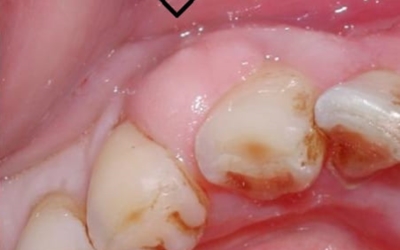

옳지 않은 형태로 자라는 사랑니는 초기엔 잇몸이 붓는 정도이지만, 나중에는 근처 어금니를 썩게 만들고 사랑니와 멀쩡한 어금니까지 통째로 발치하게 되는 불상사가 생길 수 있습니다. 사랑니의 경우 잇몸 내부쪽으로 매복해 자라는 경우도 풍부하기 때문에 치과에서 사랑니 유무를 확실히 확인할 수 있습니다.

3. 잇몸이 붓고 아플때 - 사랑니

사랑니는 치아 중 아래 위로 가장 안쪽에 나오는 어금니입니다. 사람마다 사랑니가 4개가 나는 경우가 있으며 하나가 나는 경우가 있으며, 잇몸이 붓고 아플때는 사랑니가 근처 어금니를 건드리는 옳지 않은 형태로 자라고 있을 확률이 높다고 합니다.